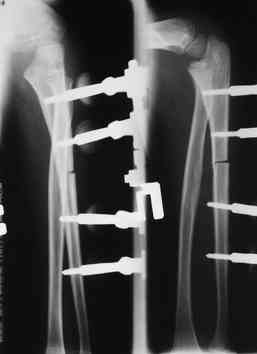

Иллюстрация к лечению застарелого повреждения Монтеджиа

Пациентка клиники детской травматологии ЦИТО

Уважаемый Абдурашид, у ребенка имеется последствие повреждения Монтеджиа. В данном случае в связи деформацией локтевой кости показано двух этпаное лечение. Первым этапом в аппарате Илизарова проводиться низведение головки лучевой кости. Вторым этапом проводится корригирующая остеотомия локтевой кости на границе средней и верхней трети с остеосинтезом либо в аппарате Илизарова, либо стержнем Богданова. Востанавливается нормальная .иогнутая форма локтевой кости. Далее проводится ревизия луче-плечевого сочленения. Иссекаются рубцовые ткани. Головка вправляется и фиксируется спицей на 3-4 недели (либо ллавсановой лентой).

Уважаемый Абдурашид! Открытое вправление головки невозможно, т.к. за 3 года головка "привыкла" к патологическому положению, а её анатомическое место уже заполнено соединительной тканью. Мальчику показано закрытое вправление головки аппаратом наружной фиксации. Мы в таких случаях накладываем Илизарова и постепенно низводим головку. После достижения репозиции можно фиксировать ещё одной спицей, а можно подержать в аппарате. С уважением, Антон Шахин, Московская ДГКБ Св. Владимира, кафедра детской хирургии РМАПО

Многоуважаемые коллеги, всем большое спасибо!!! Да, здесь было повреждение Монтеджиа, когда нарисовал скиаграмму все стало понятно. Мне очень понравились рекомендации Константина Требухина, только немножко видоизменил; я считал так, если деформацию исправить то локт/кость должна удлиниться, и во вторых, если на аппарате низвести лучевую кость, то может наступить позиционное несоответствие в дистальном радиоульнарном сочленении. 28.02.08г операция - шарнирная остеотомия локтевой кости на уровне деформации, далее вскрыт плечелучевой сустав, удалены рубцовые тканы, после исправления варусной деформации и создания физиологического изгиба локтевой кости головка луча легко вправился, из части рубцовой ткани сделана пластика кольцевндной связки, трансартикулярная фиксация спицей, локтевая кость двумя спицами.